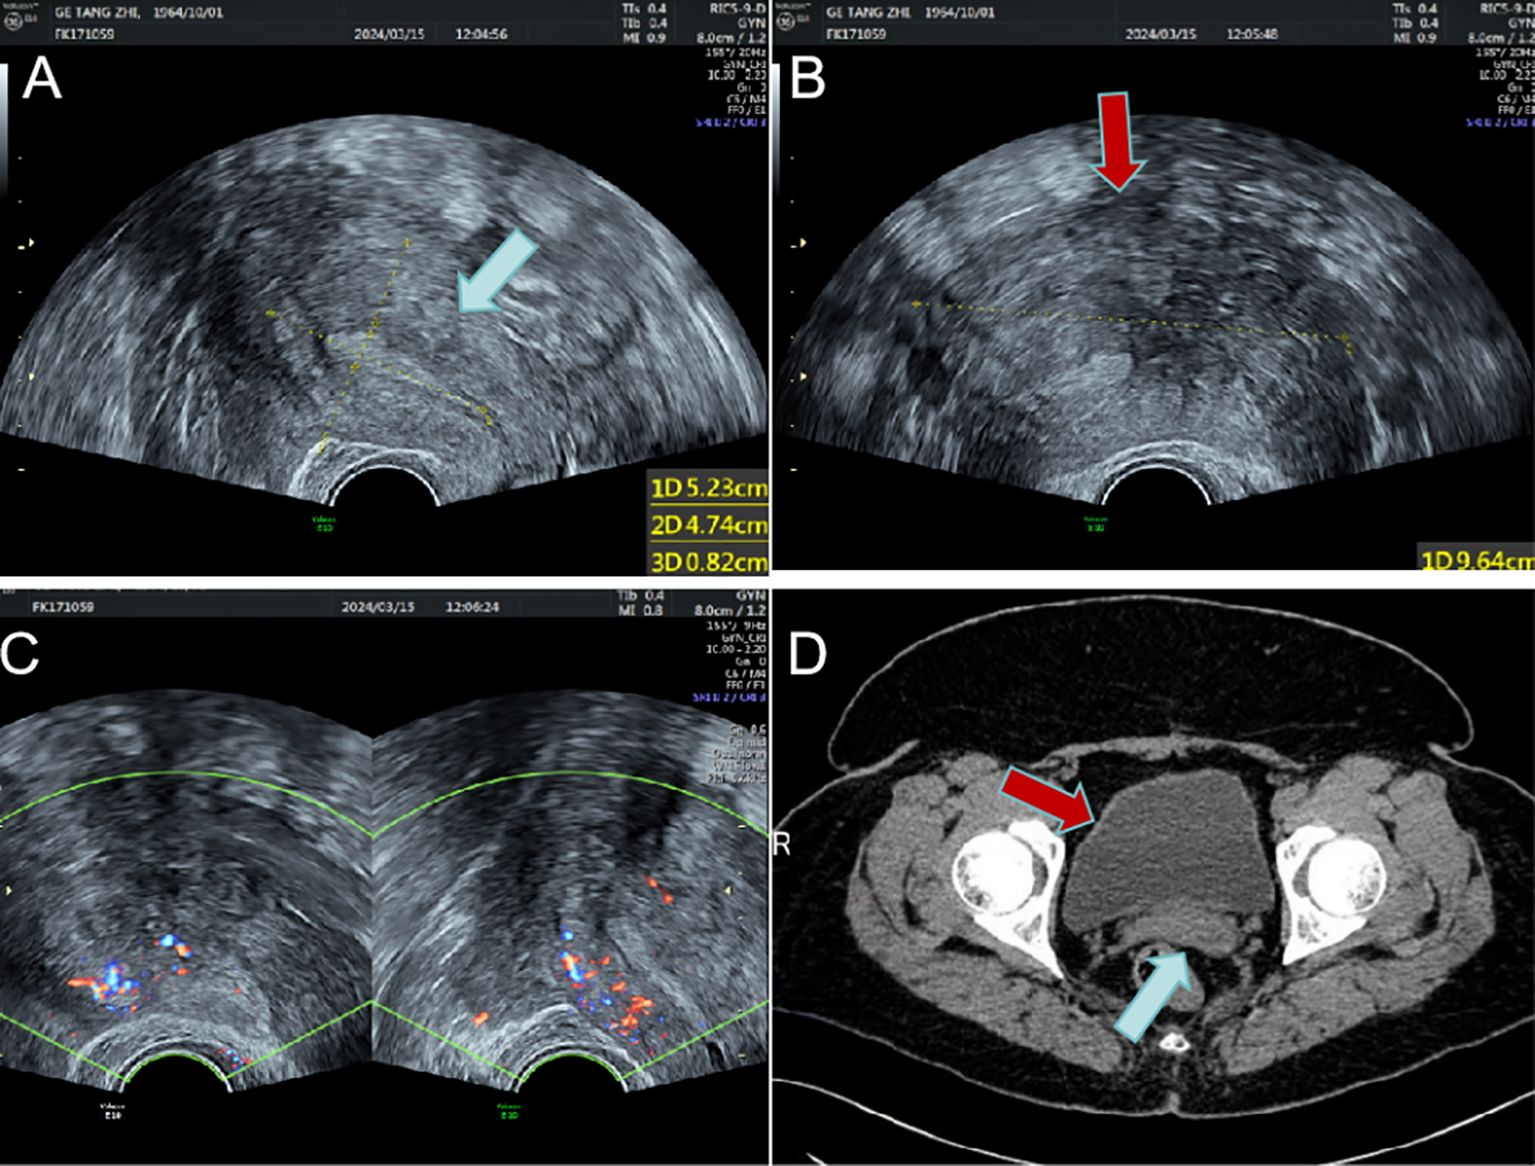

Case presentation

Figure 1

Figure 1. The uterus and the huge mass are shown on imaging. (A) Enlarged uterus on transvaginal sonography(blue arrow); (B) Large hypoechoic mass around the uterus(red arrow); (C) Blood flow signals around the uterus; (D) The uterus (blue arrow) and surrounding giant mass (red arrow) on enhanced CT.